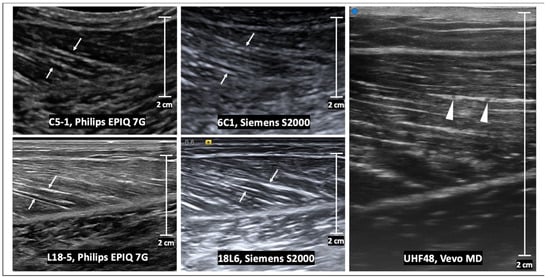

2. Normal Skeletal Muscle Anatomy on Ultrasound